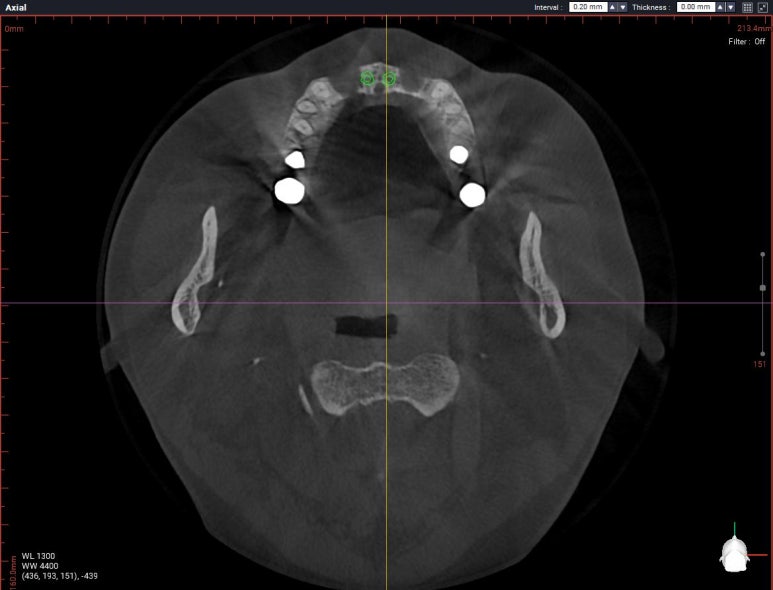

axial view를 보시면, #12,22 부위에 정말로 엄청난 골소실이 있음을 보실 수 있을겁니다.

상악 전치부 보철은 양쪽 cantilever로 할 수 밖에 없는 상황이었습니다.

다행히도 남아있는 뼈의 양은 임플란트 두개를 담기에 딱 맞는 공간이었습니다.